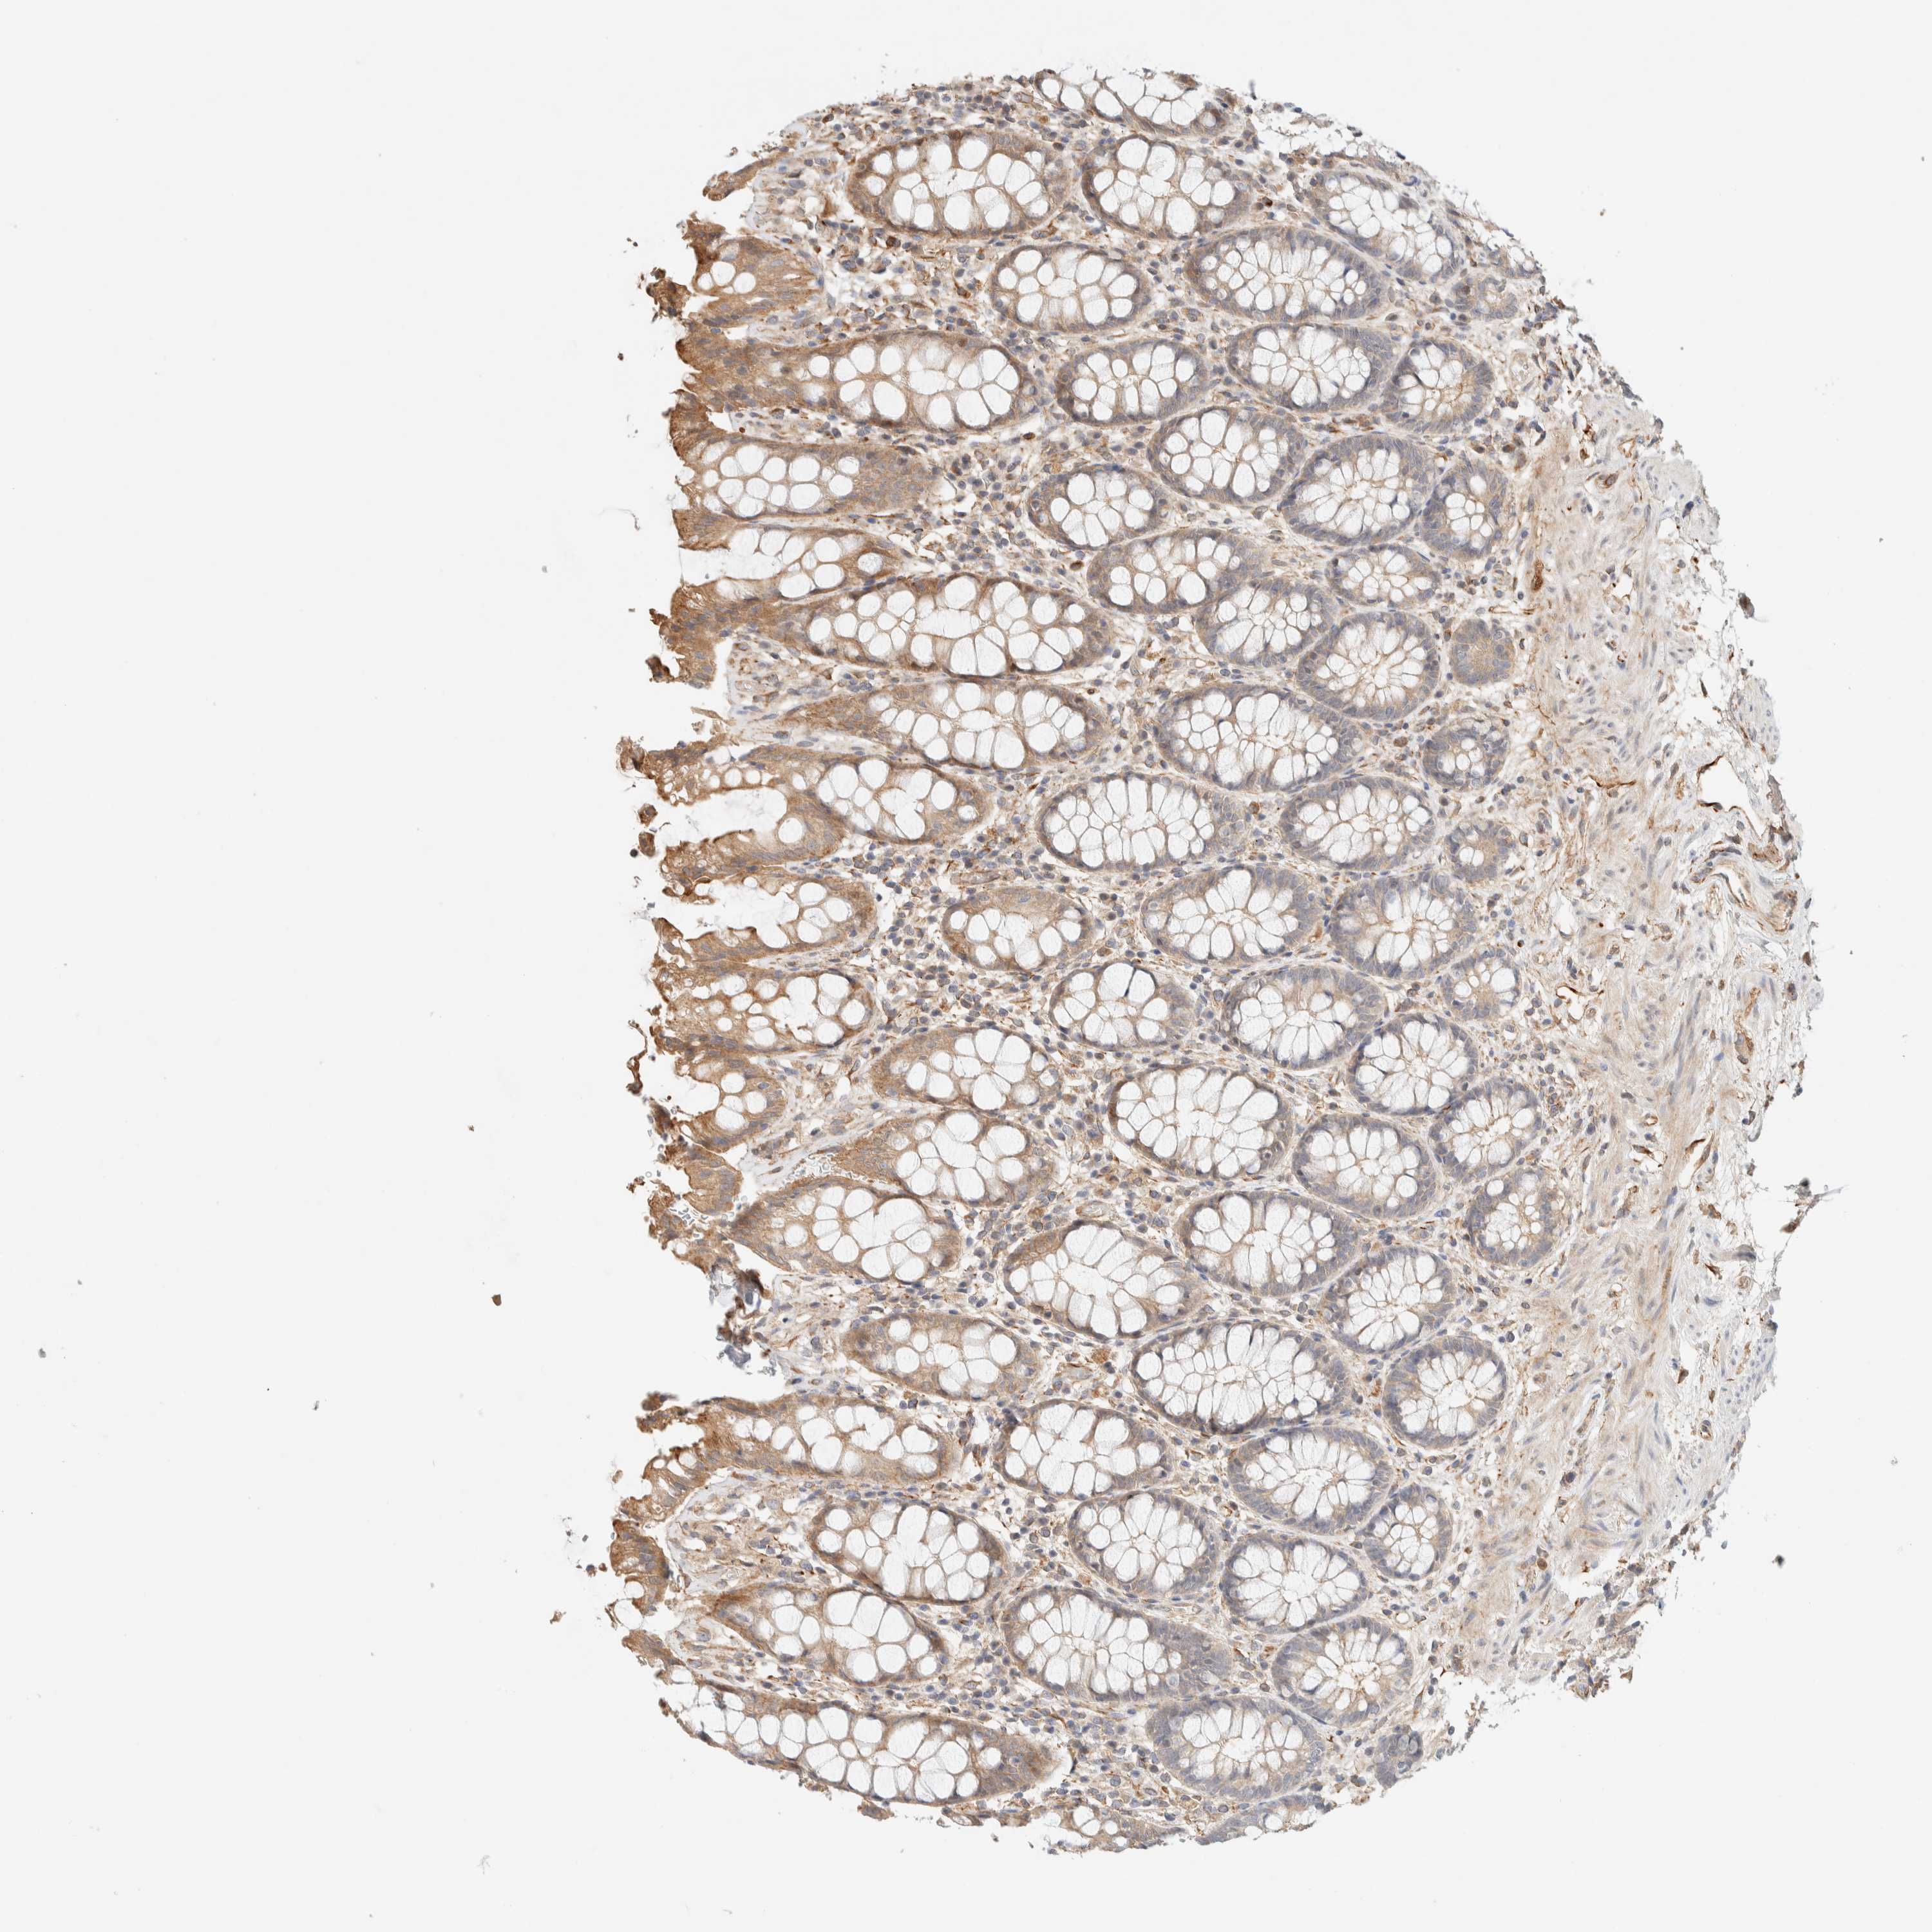

RECTUM - Antibody stainingi

Antibody staining in the annotated cell types in the current human tissue is reported as not detected, low, medium, or high, based on conventional immunohistochemistry profiling in selected tissues. This score is based on the combination of the staining intensity and fraction of stained cells.

Each image is clickable and will lead to virtual microscopy that enables deeper exploration of all samples and also displays staining intensity scores, fraction scores and subcellular localization as well as patient and tissue information for each sample.

Antibody HPA001869Antibody HPA023882

Glandular cells MediumMedium